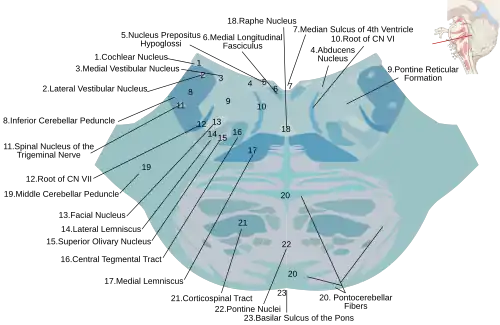

Horizontal section through the lower part of the pons. The medial lemniscus is labeled #17.

Horizontal section through the lower part of the pons. The medial lemniscus is labeled #17. -